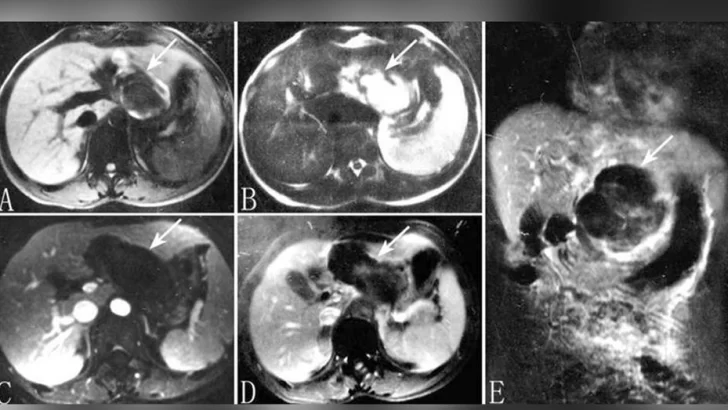

Entonces se procedió a hacerle un ecografía que reveló que había un bebé en su hígado.

Tenía una versión extremadamente rara de un embarazo ectópico, en el que "un óvulo fertilizado se implanta y crece fuera de la cavidad principal del útero", de acuerdo con los datos de la Clínica Mayo.

Sin embargo, el caso de esta paciente era aún más raro, ya que el embrión "acabó viajando hasta el hígado, donde se implantó", señaló el médico.